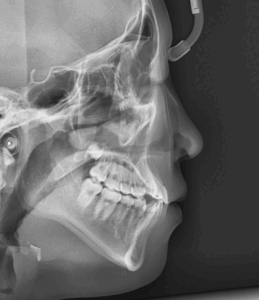

MARPE 악궁 확장을 통한 안면 골격 비대칭, 횡적 부조화(transverse discrepancy) 개선 과정

오늘은 진단이 다소 어려운 케이스인 '횡적 부조화'에 대한 내용을 설명해보려 합니다. ​ 전문적인 내용이라 살짝 이해하기 어려우실수도 있겠지만.. ​ 실제 케이스와 함께 최대한 쉽게 풀어서 설명드리도록 하겠습니다. 『불편하고 어딘가 불안정한…